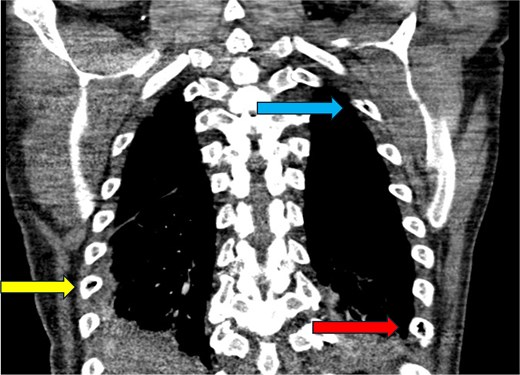

CT abdomen and pelvis—coronal plane. Intraosseous gas is visualized in the L1 vertebral body (yellow arrow, top middle) and left proximal femoral shaft to the level of the greater trochanter (blue arrow, bottom right). These sites are exemplary of the classic “pumice stone” sign, which is pathognomonic of emphysematous osteomyelitis [7]. Soft tissue gas is also seen in the right adductor longus (red arrow, bottom left). Soft tissue gas is commonly seen adjacent to involved bones in emphysematous osteomyelitis [7]. This patient has significant intraosseous gas of the right pubic ramus, although this is not visualized on this section.

CT chest—coronal plane. Intraosseous gas is seen within the right sixth rib (yellow arrow, bottom left), left second rib (blue arrow, top right), and left eighth rib (red arrow, bottom right).